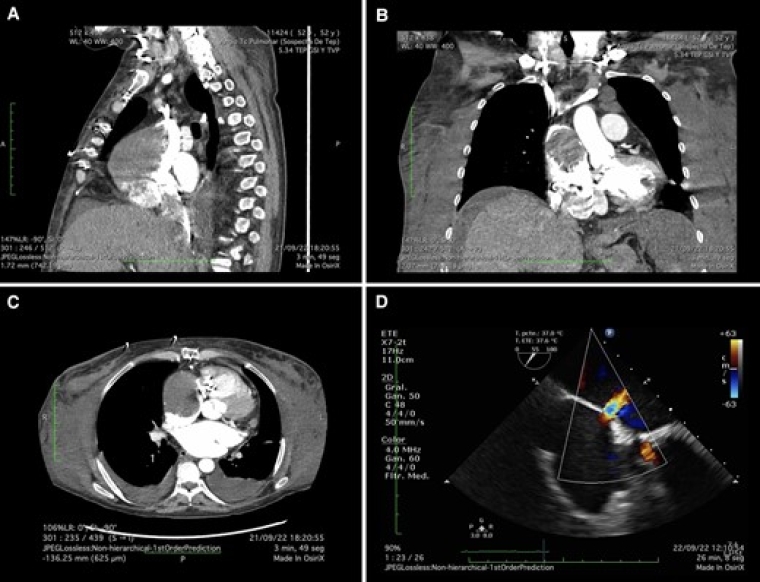

A 44-year-old man with a history of hypertension and smoking arrived at the emergency department with a 2-day history of oppressive chest pain associated with diaphoresis and nausea. Physical examination revealed high blood pressure (170/100 mmHg) and no signs of heart failure. Serial 12-lead electrocardiogram showed dynamic changes of T wave in V5 and V6, and high-sensitivity cardiac troponin levels were increased (443 ng/mL). Point-of-care ultrasound (POCUS) was performed at the bedside showing the following findings:

What is the likely aetiology of this patient’s chief complaint?

- Coronary sinus calcification

- Retroaortic coronary artery

- Septal communication

- Intra-myocardial dissection